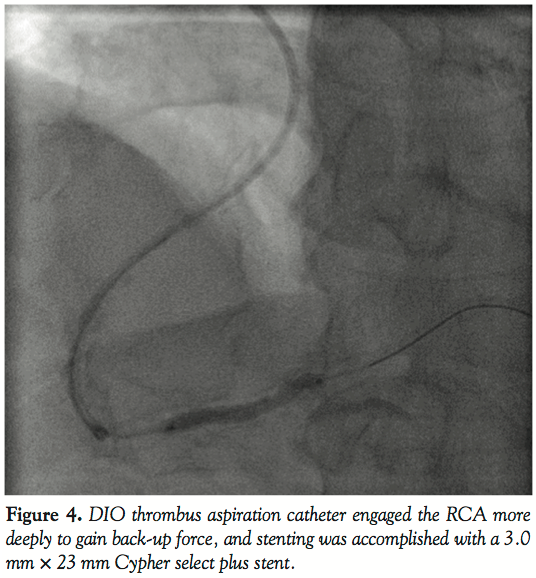

In an effort to insert the intravascular ultrasound catheter up to the mid portion of the RCA, we engaged the RCA more deeply using the DIO thrombus aspiration catheter to gain back-up force. Stenting was accomplished with a 3.0 mm × 23 mm Cypher select plus stent (Cordis, Johnson and Johnson Interventional System) delivered at 14 atm. The residual stenosis was less than 5%. This excellent result was accomplished by deep engagement using a DIO thrombus aspiration catheter.